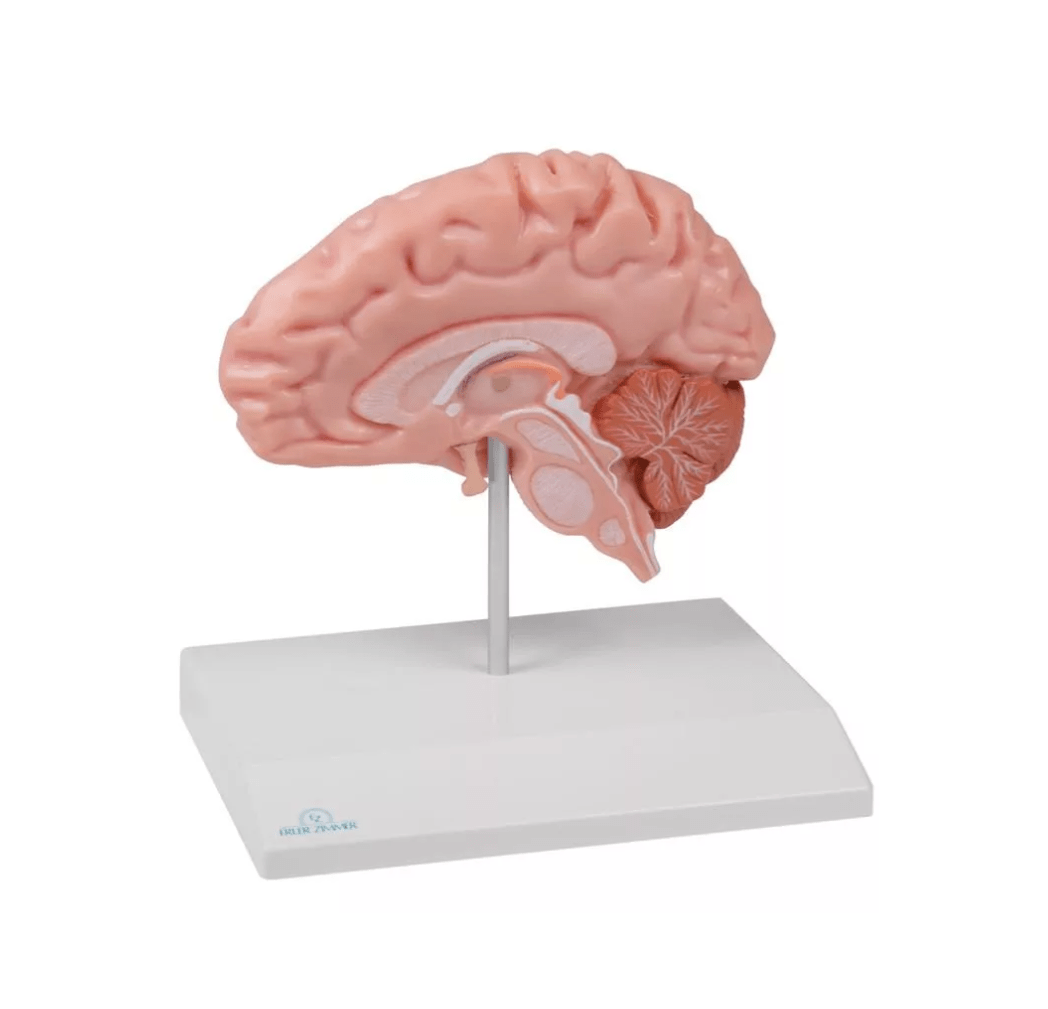

Erler-Zimmer

Anatomische Gehirnhälfte, lebensgroß

Artikelnummer: SKU: EZC915

PZN: PZN:

Packaging unit: VE:

Auf Lager: In 1–3 Werktagen geliefert

★★★★★ 0 Bewertungen79,00 €79,00 €79,00 € -